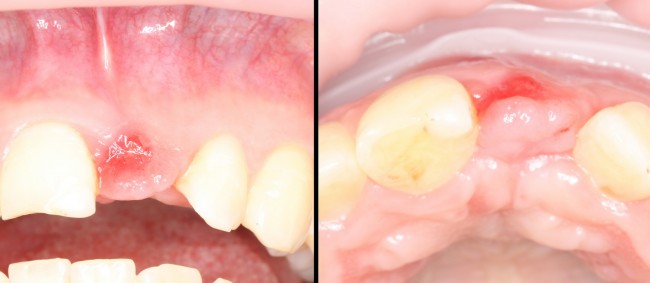

Через год после травмы, девушка обратилась в нашу клинику для восстановления отсутствующего зуба. К тому моменту у нее уже был временный съемный протез, изготовленный в вышеозначенном стоматологическом кабинете, ну и, вот какая клиническая картина:

Хочу спросить вас, уважаемые друзья, можно ли в таком состоянии и при таких объемах альвеолярного гребня поставить имплантат в область отсутствующего зуба? Безусловно, можно. Для этого нужно просто взять имплантат потоньше и поставить его подальше, в сторону неба — и он нормально интегрируется.

Возможно ли получить на подобном импланте более-менее приемлемый эстетический и функциональный результат? Вряд ли. Если за пределами эстетически значимой зоны мы можем пойти на эстетические компромиссы (все равно никто не увидит), то проблемы с эстетикой в области передней группы зубов… да еще у девушки…. так можно человеку всю личную жизнь испортить.

Через 3 месяца мы готовы приступить к формированию десны. И каким-то невероятным образом, у нас получился даже избыток слизистой оболочки. Что, безусловно, очень даже хорошо:

По фотографии хорошо видно, как изменилась форма альвеолярного гребня после операции.